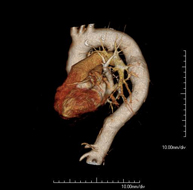

- Angio-TC aorta abdominal  Prueba diagnóstica no invasiva que consiste en el estudio de la arteria aorta abdominal obteniendo imágenes de alta definición anatómica mediante el empleo de un equipo de TC (Tomografía Computarizada) y de contraste yodado. La calidad de las imágenes permite realizar reconstrucciones en 2D y 3D gracias a estaciones de trabajo especializadas en el estudio arterial. Está indicado en aquellos pacientes con enfermedad vascular (aterosclerosis), en aneurismas de aorta, en pacientes con dolor abdominal de posible origen vascular, en estudios pre-quirúrgicos de lesiones adyacentes a la aorta abdominal como "mapa" vascular, etc. La información obtenida de forma no invasiva es indispensable para los pacientes que requieren tratamiento percutáneo o quirúrgico. En aquellos pacientes que solo requieren un seguimiento de las lesiones vasculares, esta técnica es la técnica no invasiva de elección junto con la angio-RM. Prueba diagnóstica no invasiva que consiste en el estudio de la arteria aorta abdominal obteniendo imágenes de alta definición anatómica mediante el empleo de un equipo de TC (Tomografía Computarizada) y de contraste yodado. La calidad de las imágenes permite realizar reconstrucciones en 2D y 3D gracias a estaciones de trabajo especializadas en el estudio arterial. Está indicado en aquellos pacientes con enfermedad vascular (aterosclerosis), en aneurismas de aorta, en pacientes con dolor abdominal de posible origen vascular, en estudios pre-quirúrgicos de lesiones adyacentes a la aorta abdominal como "mapa" vascular, etc. La información obtenida de forma no invasiva es indispensable para los pacientes que requieren tratamiento percutáneo o quirúrgico. En aquellos pacientes que solo requieren un seguimiento de las lesiones vasculares, esta técnica es la técnica no invasiva de elección junto con la angio-RM.

- Angio-TC aorto-ilíaco Prueba diagnóstica no invasiva que consiste en el estudio de las arterias ilíacas y la aorta abdominal obteniendo imágenes de alta definición anatómica mediante el empleo de un equipo de TC (Tomografía Computarizada) y de contraste yodado. La calidad de las imágenes permite realizar reconstrucciones en 2D y 3D gracias a estaciones de trabajo especializadas en el estudio arterial. Esta prueba está especialmente indicada como estudio pre-quirúrgico (mapa vascular) antes de intervenciones percutáneas o quirúrgicas de aorta abdominal, como el estudio complementario en pacientes con isquemia de miembros inferiores, etc. Prueba diagnóstica no invasiva que consiste en el estudio de las arterias ilíacas y la aorta abdominal obteniendo imágenes de alta definición anatómica mediante el empleo de un equipo de TC (Tomografía Computarizada) y de contraste yodado. La calidad de las imágenes permite realizar reconstrucciones en 2D y 3D gracias a estaciones de trabajo especializadas en el estudio arterial. Esta prueba está especialmente indicada como estudio pre-quirúrgico (mapa vascular) antes de intervenciones percutáneas o quirúrgicas de aorta abdominal, como el estudio complementario en pacientes con isquemia de miembros inferiores, etc.